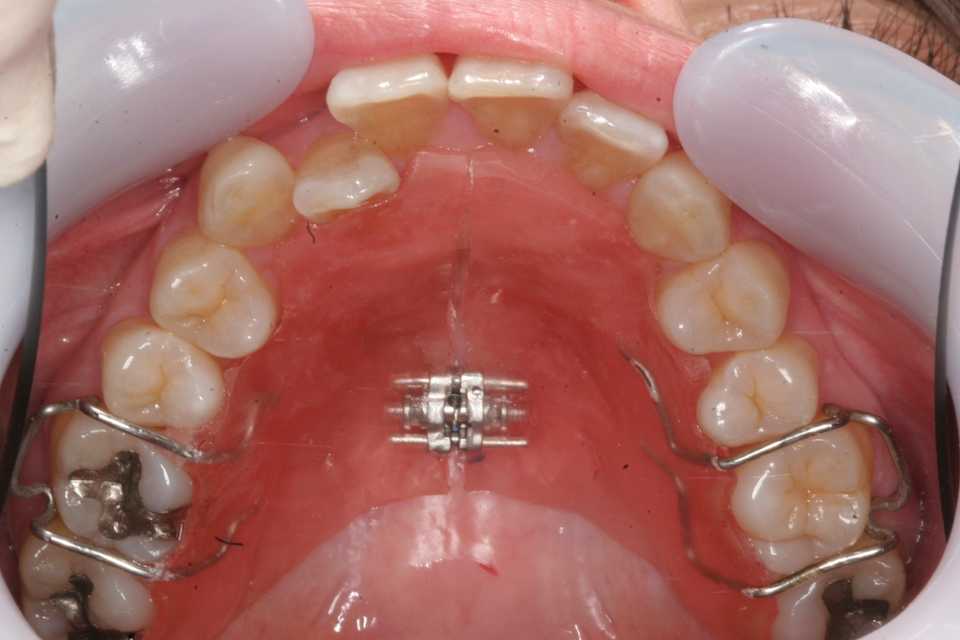

40代女性、左上2、クロスバイト前回のつづきhttps://plaza.rakuten.co.jp/mabo400dc/diary/202509290000/ブラケットワイヤー装着から3ヶ月ほどで改善する、その後は患者の細かい要望に応じたりしながら微調整と保定に入る準備をする。いきなりブラケット&ワイヤーを除去することはできない。歯槽骨が動かした直後はゆるゆるなので、どうなるか分からない。後戻りしたり、思いっきり歯列が歪んだりする。最低でも2年くらいは用心しないと悲惨なことになる。2025/04/01拡大症装置を2年程使って十分広がって、動かすスペースができたのでブラケット&ワイヤーを装着した。最初はレベリングと言ってブラケットのスロット(ワイヤーの入る溝)を一列にする工程。ワイヤーは丸014"左右の3456は動かす必要はないので、スーパーボンドで歯列固定している。奥歯全部をアンカーに使えるし、患者も術者も楽だ。歯列狭窄が元に戻らないように床装置は入れている。https://plaza.rakuten.co.jp/mabo400dc/diary/202509260000/2025/04/26隙間をパワーチェインで引っ張って寄せる2025/05/20左上2番の先が引っかかっているので、太めの丸ワイヤー016"に交換した。2025/06/18被蓋は改善したので微調整に入る。動かす必要のないところは連続結紮しておく。角ワイヤーの016"-016"2025/08/26床装置はそのまま保定装置として使える。

40代女性、左上2、クロスバイト子供の頃から気にしていて、コンプレックスに悩まされていたらしい。この方のお姉さんに聞いて初めて知った。矯正をしたいと依頼があったので、歯列を広げることから始めたのだが、僕はあまり気にしていなかったので、しばらく忘れて放置していた。その話を聞いて本格的に始めた経緯がある。前回のつづきhttps://plaza.rakuten.co.jp/mabo400dc/diary/202509250000/今年になってバタバタとブラケット装着して歯列矯正を始めた印象があるのだが、画像を調べてみると2016年から始めていた。真面目に四六時中上下の拡大装置を装着していただいて、1年後の2017年にはかなり歯列が拡大した。その後僕が忘れていて、2023年から治療を再開した。今日はそこまで。2016/02/292017/04/10かなり開いているのが見えると思う。この間ブランク、拡大装置の装着はしていただいていた。拡大装置の再作成。もう少し歯列拡大することにした。2023/05/242025/04/01ブラケット&ワイヤーを装着して2番の被蓋を改善するには歯列をもっと広げてスペースを作るしかない。もしくは抜歯してスペースを作るのだが、それはしたくない。歯列を広げるには真面目に拡大装置を装着しても2年かかる。次回はブラケットの選択などブラケット&ワイヤーの基本から。歯学部を出ただけでは全く分からない。歯科矯正学の大学院に進学したり医局に入ってご奉公するしかない。それも人気が高く入れてもらえない。セミナーに参加すると数十万円かかる。ここでは無料公開だwつづく

40代女性、左上2、クロスバイト子供の頃から気にしていて、コンプレックスに悩まされていたらしい。この方のお姉さんに聞いて初めて知った。矯正をしたいと依頼があったので、歯列を広げることから始めたのだが、僕はあまり気にしていなかったので、しばらく忘れて放置していた。その話を聞いて本格的に始めた経緯がある。最近はマウスピース矯正が流行って、こういう症例も矯正専門医でなくても治療を提供できることが視野に入って来ている。しかし、元々歯列が狭い症例で、非抜歯でするには初めに歯列を広げる処置をしなくてはならないのだが、歯列が狭くなる根本原因は実はあまり知られていないというか、矯正専門医も気にしていないフシがある。この歯列が狭くなる根本原因は横向き寝、うつ伏せ寝、頬杖等の態癖と呼ばれる顎に加わる外力によるものだ。例え歯列矯正が終わったとしても態癖が治らないとまた元に戻ってしまう。この態癖対策が難しい。ここでご紹介している部分矯正をマスターすれば矯正専門医でなくても非抜歯でこのような症例に対応できるので患者の信頼度は増すと思う。是非取り入れていただきたい。とりあえずbefore/after から。歯列が広がってきていることが分かると思う。beforeafterつづく